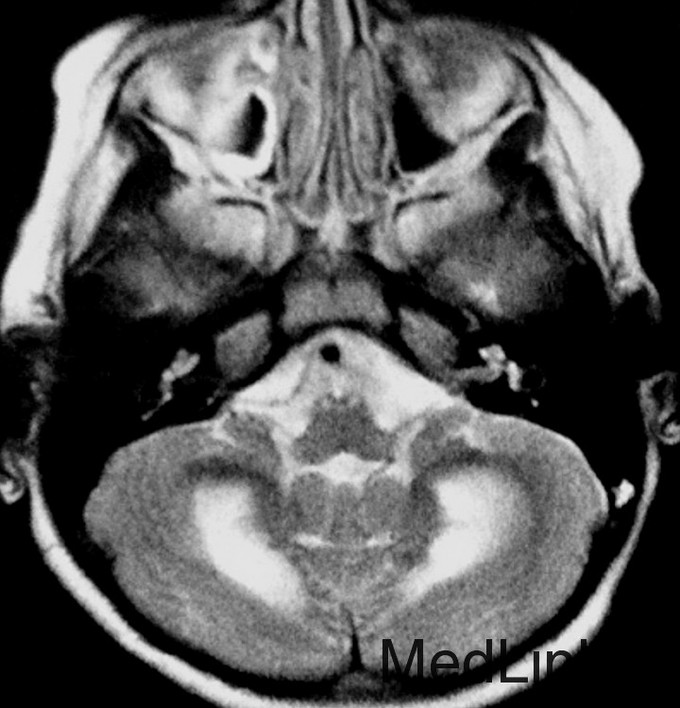

神经科查体显示肌僵直,腱反射亢进,双侧病理征阳性,轻度的小脑共济失调,振动觉及本体觉异常。CSF正常。 T2WI显示幕上及幕下白质T2高信号。内囊后肢、脑干皮质脊髓束、小脑中脚均受累。脊髓T2WI可见皮质脊髓侧束T2高信号。